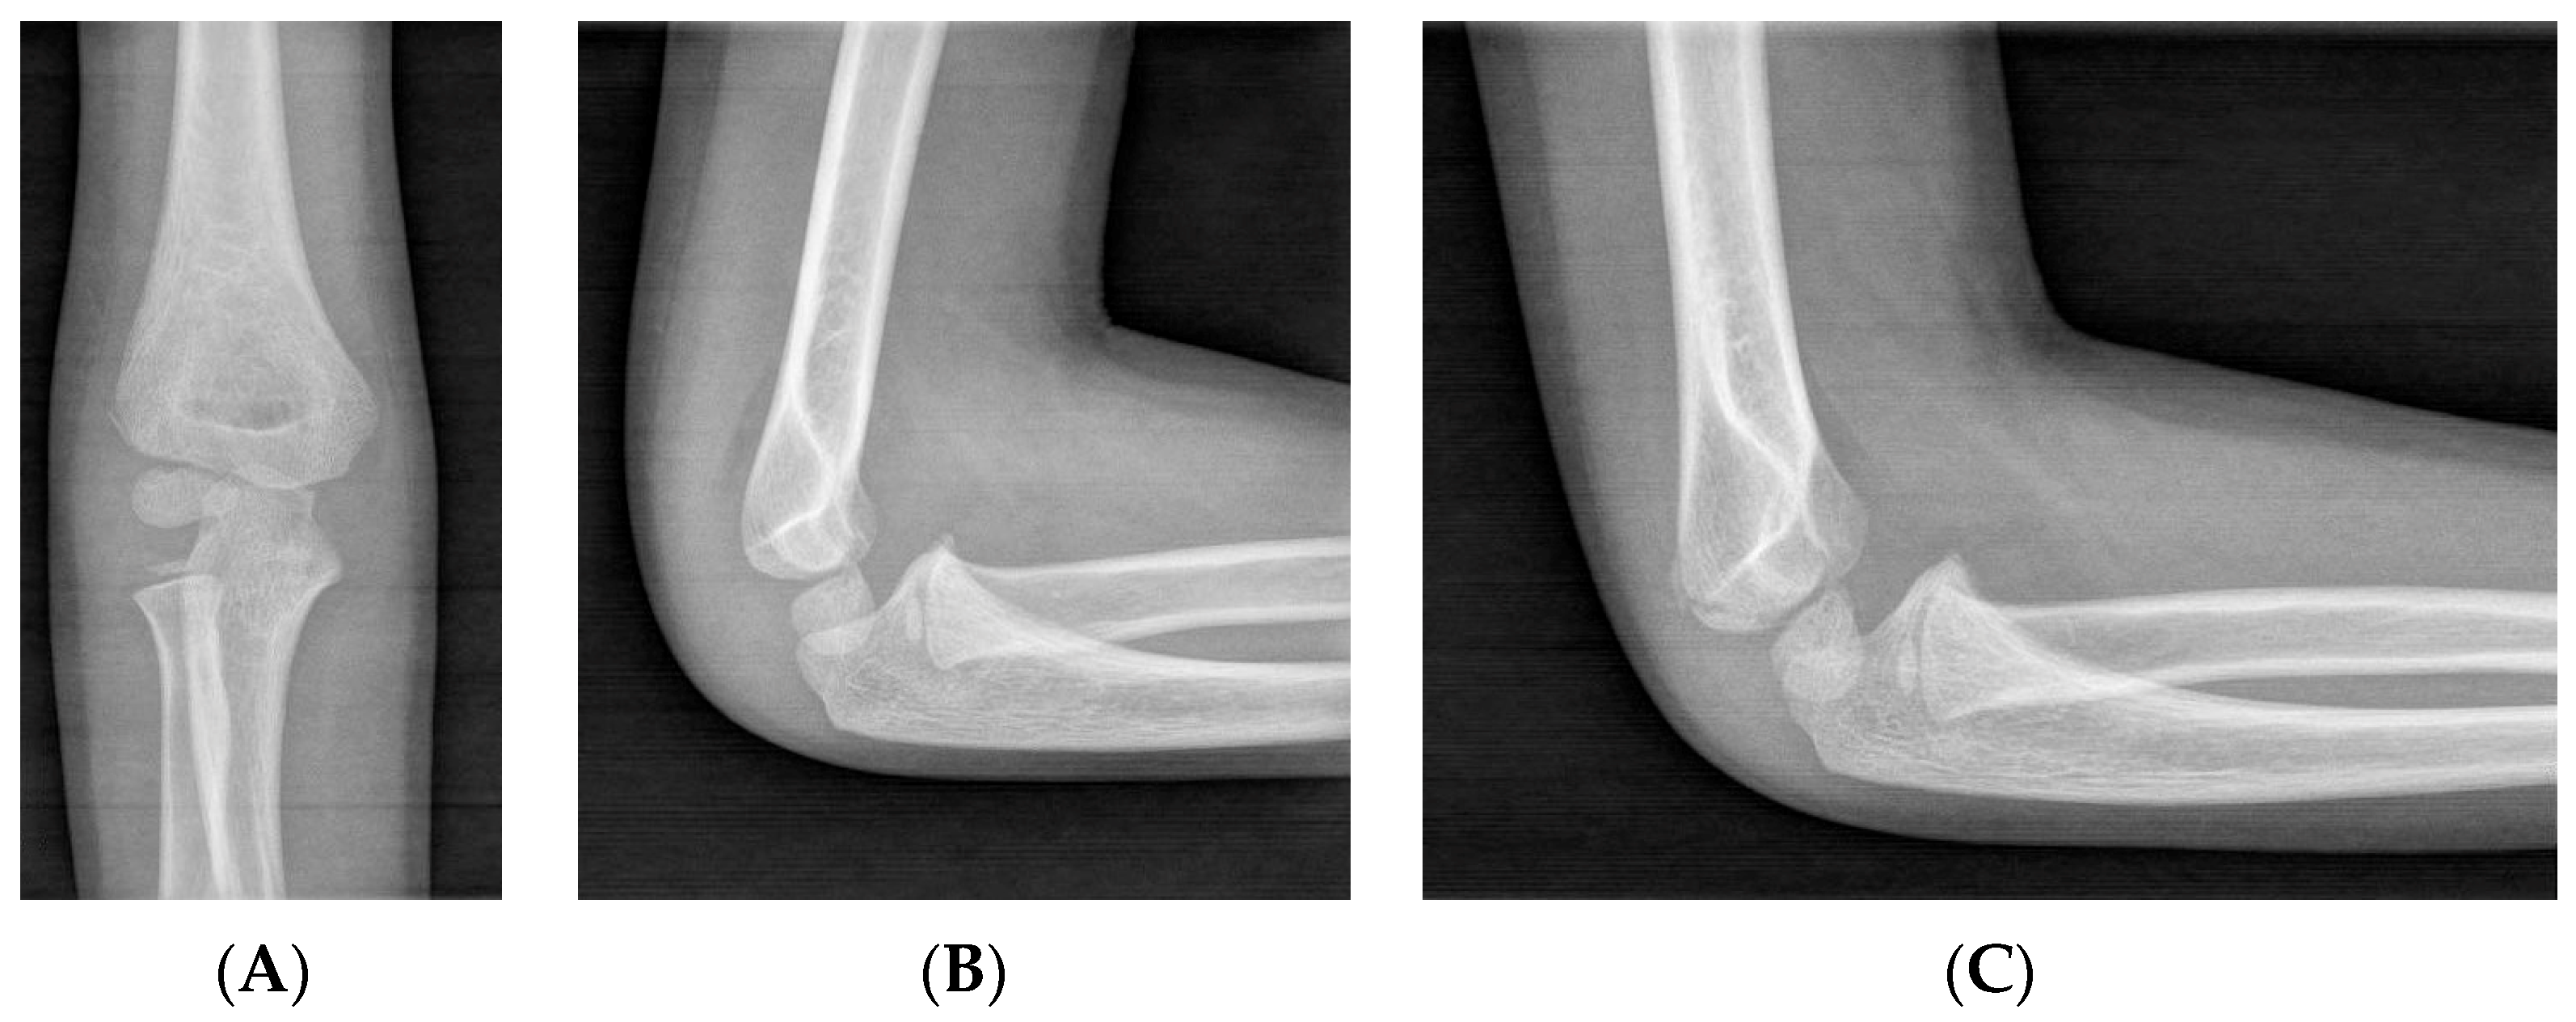

Currently, X-ray remains the diagnostic gold standard for pediatric LHC fractures, with general recommendations including obtaining an anteroposterior (AP) view and a lateral view. While some specialists suggest that an additional internal oblique radiograph should be used in cases of uncertainty, others recommend its routine use, as it can provide a clearer view of fracture displacement (Figure 1). This issue should be emphasized to residents and young surgeons, highlighting the need for a high index of suspicion of an LHC fracture when encountering a patient with elbow pain and functional impairment. If necessary, comparison with an X-ray of the contralateral elbow can be performed [19,20,21].

Figure 1.

Non-displaced LHC fracture, for which conservative treatment is recommended. (A) An AP view, where the fracture is vaguely visible. (B) A lateral view, where the fracture is not appreciable. (C) An internal oblique view, where the characteristics of the fracture are clearly distinguishable.

Radiographic diagnosis can be challenging due to factors related to the age of the patients. Pediatric patients in pain may not fully cooperate during imaging, while the incompletely ossified epiphysis can complicate fracture identification, especially when there is no or minimal displacement [19,20,21].